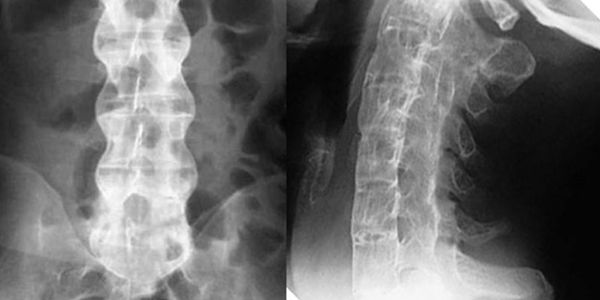

- Chụp X-quang tư thế thẳng và nghiêng để phát hiện các cột sống bị hẹp, hẹp lỗ liên hợp đốt sống, gai xương sống.

Hình ảnh: Chuẩn đoán điều trị bệnh thoái hóa cột sống thắt lưng